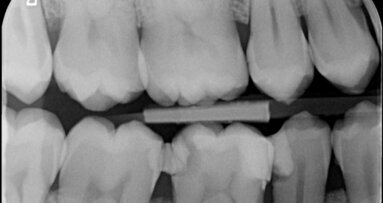

Vier jaar geleden meldde zich een patiënt in onze praktijk met heftige pijn in de regio 46. Na een blik op de bitewing en op de apicale röntgenopname ...